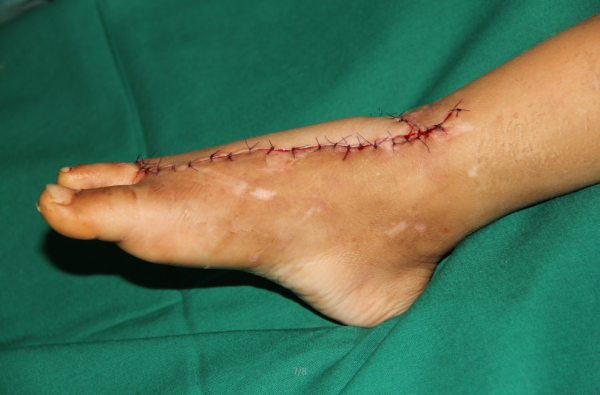

今天做的游离腹股沟,2岁幼儿,机器绞伤,足背组织缺损术前

QQ截图20161102215228.png

设计

QQ截图20161102215149.png

切取

QQ截图20161102215214.png

QQ截图20161102215248.png

术后外观满意

QQ截图20161102215321.png

QQ截图20161102215333.png

QQ截图20161102215349.png

供区直接缝合

QQ截图20161102215304.png